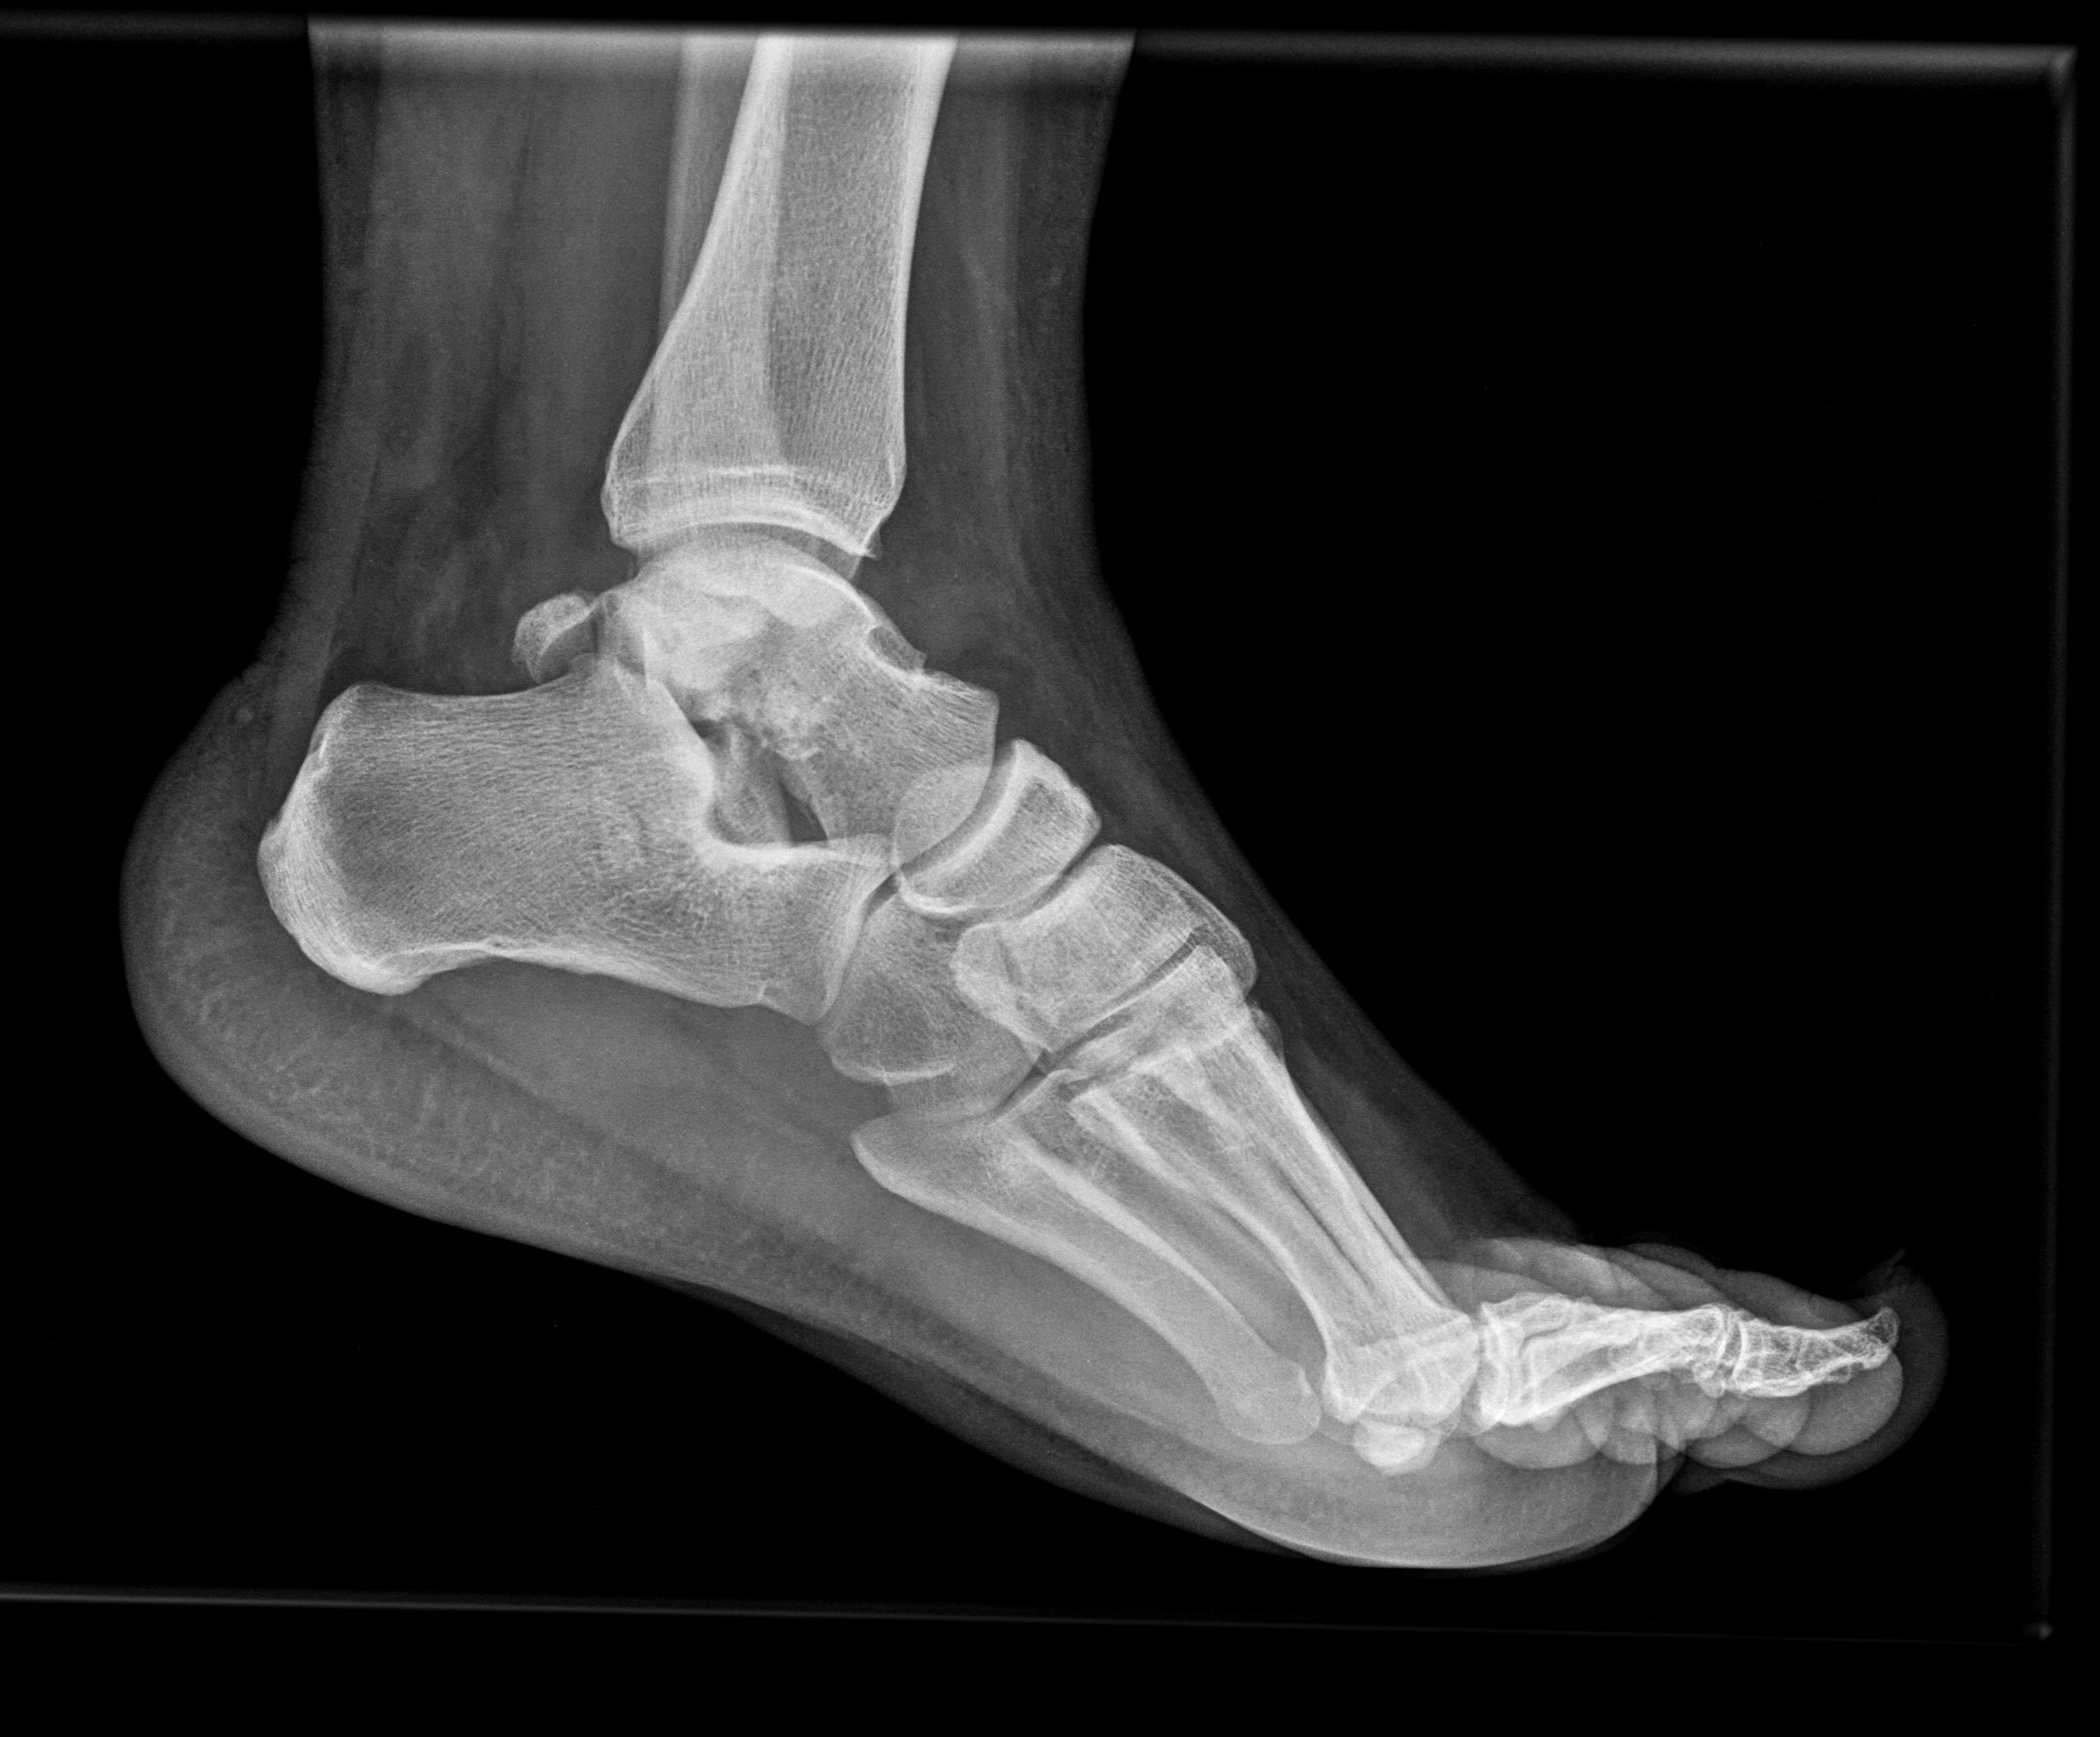

Anteroposterior, mortise and true lateral views of the left foot and ankle radiographs were obtained (Figure 1 and Figure 2). A displaced lateral talar body fracture and subtalar joint disruption, as well as a tilt of the tibiotalar joint, were revealed from the plain radiographs. Osteochondral defect on the medial side of the dome of the talus, due to an old ankle injury, sustained few years ago, was also visible. CT scan of the left foot confirmed a displaced lateral talar body fracture along with a displaced sustentaculum tali fracture (Figure 3, Figure 4 and Figure 5).

Figure 2: Foot and Ankle true lateral view. Sustentaculum tali fracture and subtalar disruption due to talar body fracture is identified. View Figure 2